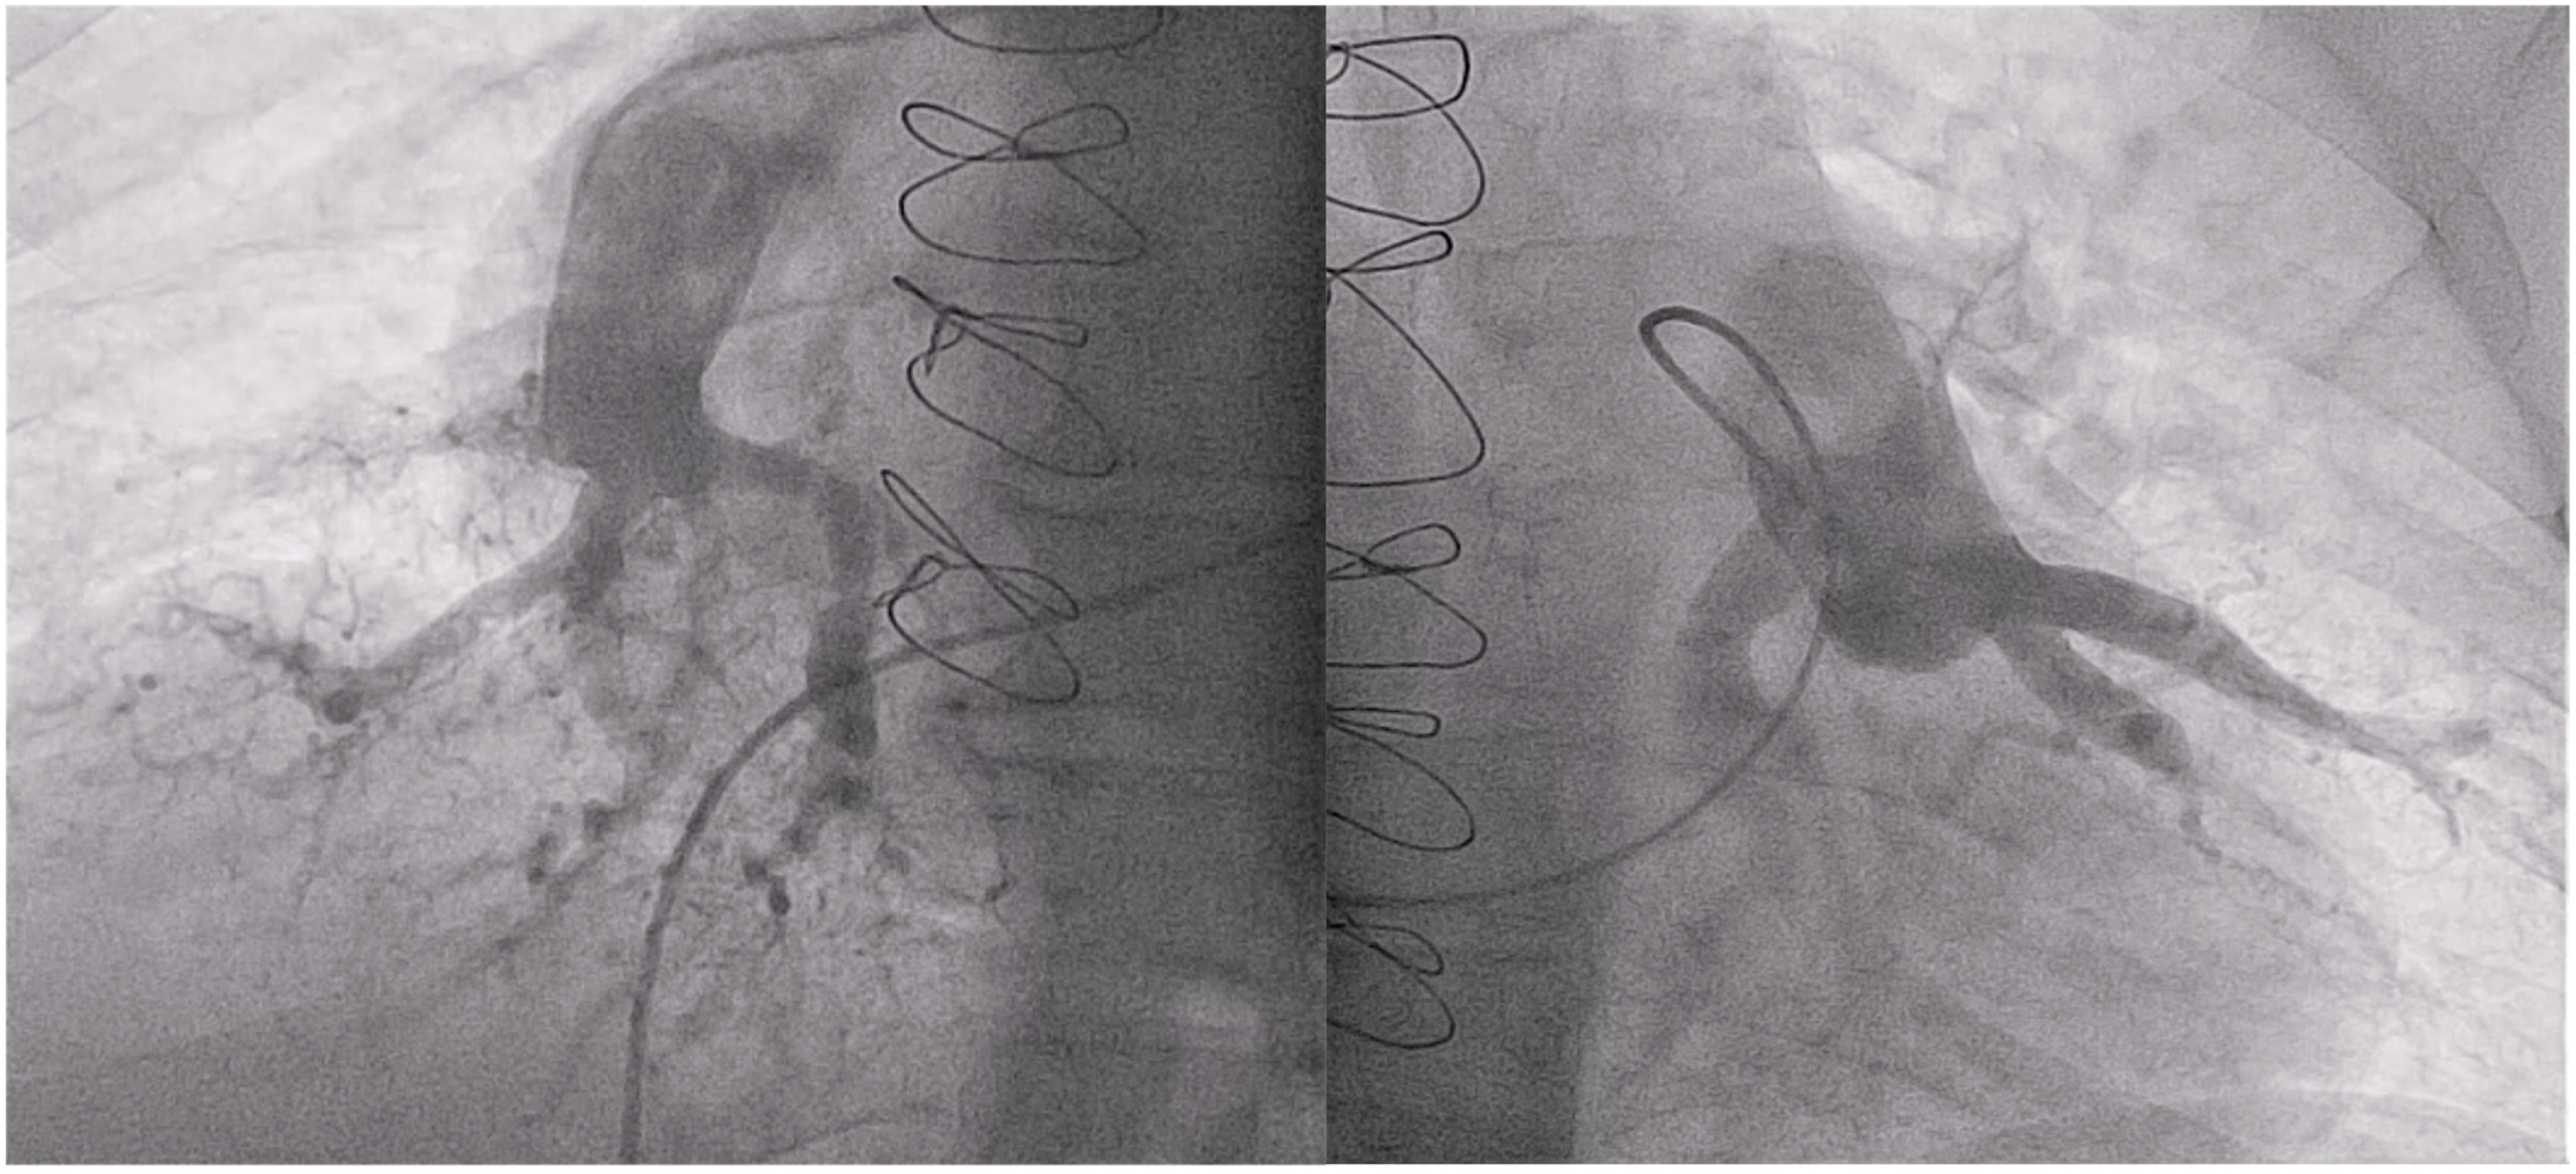

2.2. Balloon Pulmonary Angioplasty Procedure

- Velázquez, M.; Maneiro, N.; Lareo, A.; Albarrán, A.; Huertas, S.; Olazábal, A.; Delgado, J.; Alonso, S.; Sarnago, F.; Tejada, J.G.; et al. Selective Segmental Pulmonary Angiography: Anatomical, Technical and Safety Aspects of a Must-Learn Technique in Times of Balloon Pulmonary Angioplasty for Chronic Thromboembolic Pulmonary Hypertension. J. Clin. Med. 2021, 10, 3358. [Google Scholar] [CrossRef] [PubMed]

- Kawakami, T.; Ogawa, A.; Miyaji, K.; Mizoguchi, H.; Shimokawahara, H.; Naito, T.; Oka, T.; Yunoki, K.; Munemasa, M.; Matsubara, H. Novel Angiographic Classification of Each Vascular Lesion in Chronic Thromboembolic Pulmonary Hypertension Based on Selective Angiogram and Results of Balloon Pulmonary Angioplasty. Circ. Cardiovasc. Interv. 2016, 9, e003318. [Google Scholar] [CrossRef] [PubMed]